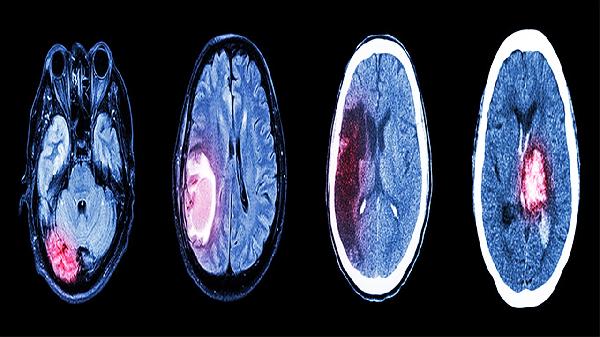

头部摔伤引起颅内出血会有哪些后遗症

头部摔伤引起颅内出血可能导致运动障碍、认知功能下降、语言障碍、癫痫发作、情绪行为异常等后遗症。颅内出血的严重程度与出血部位、出血量等因素有关,部分患者可能遗留长期功能障碍。

颅内出血后3-6个月是黄金康复期,建议在专业康复医师指导下进行系统性功能训练。日常需控制血压血糖,避免头部再次受伤,保证充足睡眠并保持情绪稳定。定期复查头颅CT或MRI监测脑组织恢复情况,出现头痛加重、意识模糊等异常症状时需立即就医。